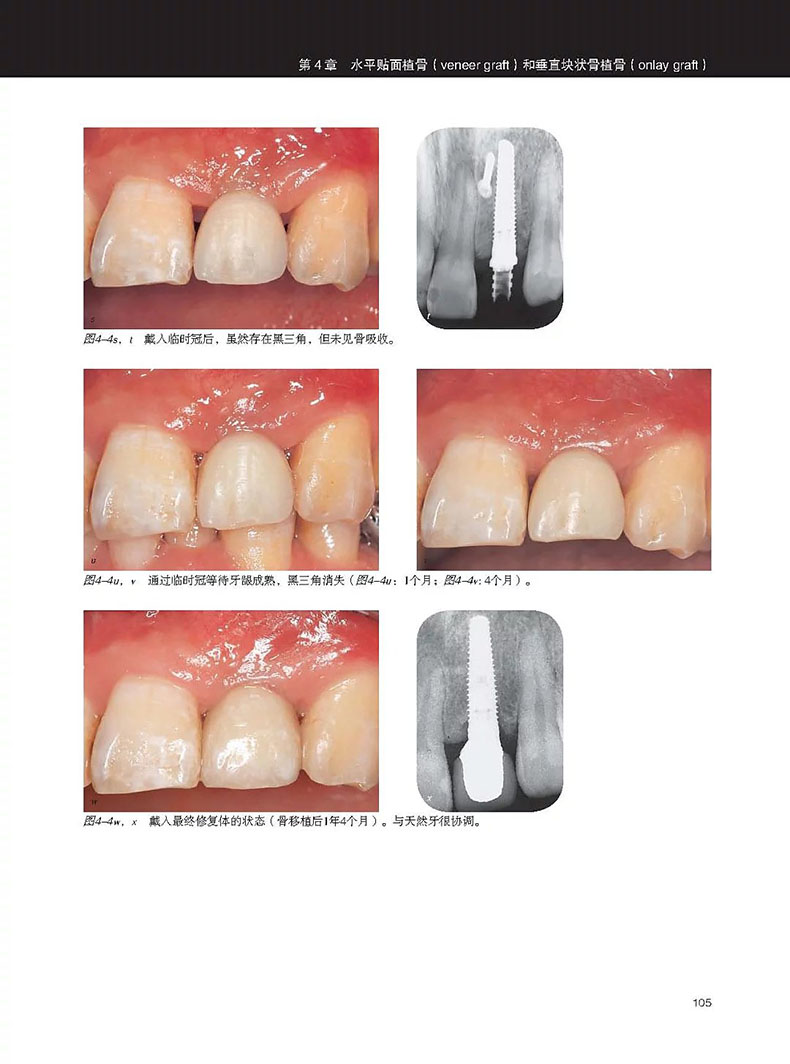

單顆上前牙缺失